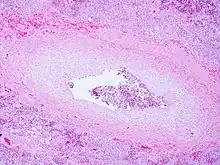

Pulmonary veno-occlusive disease-Intimal fibrosis with marked narrowing of lumen of a large pulmonary vein | |

Pulmonary veno-occlusive disease may have a genetic basis. Published reports have indicated fatal occurrences that appeared to possess a familial pattern, more to the point, a germline mutation.[7] The pathophysiology of veno-occlusive disease culminates in occlusion of the pulmonary blood vessels. This could be due to edematous tissue (sclerotic fibrous tissue). Thickening is identified in lobular septal veins, also dilatation of lymphatics happens. Furthermore, alveolar capillaries become dilated (due to back-pressure).[8]